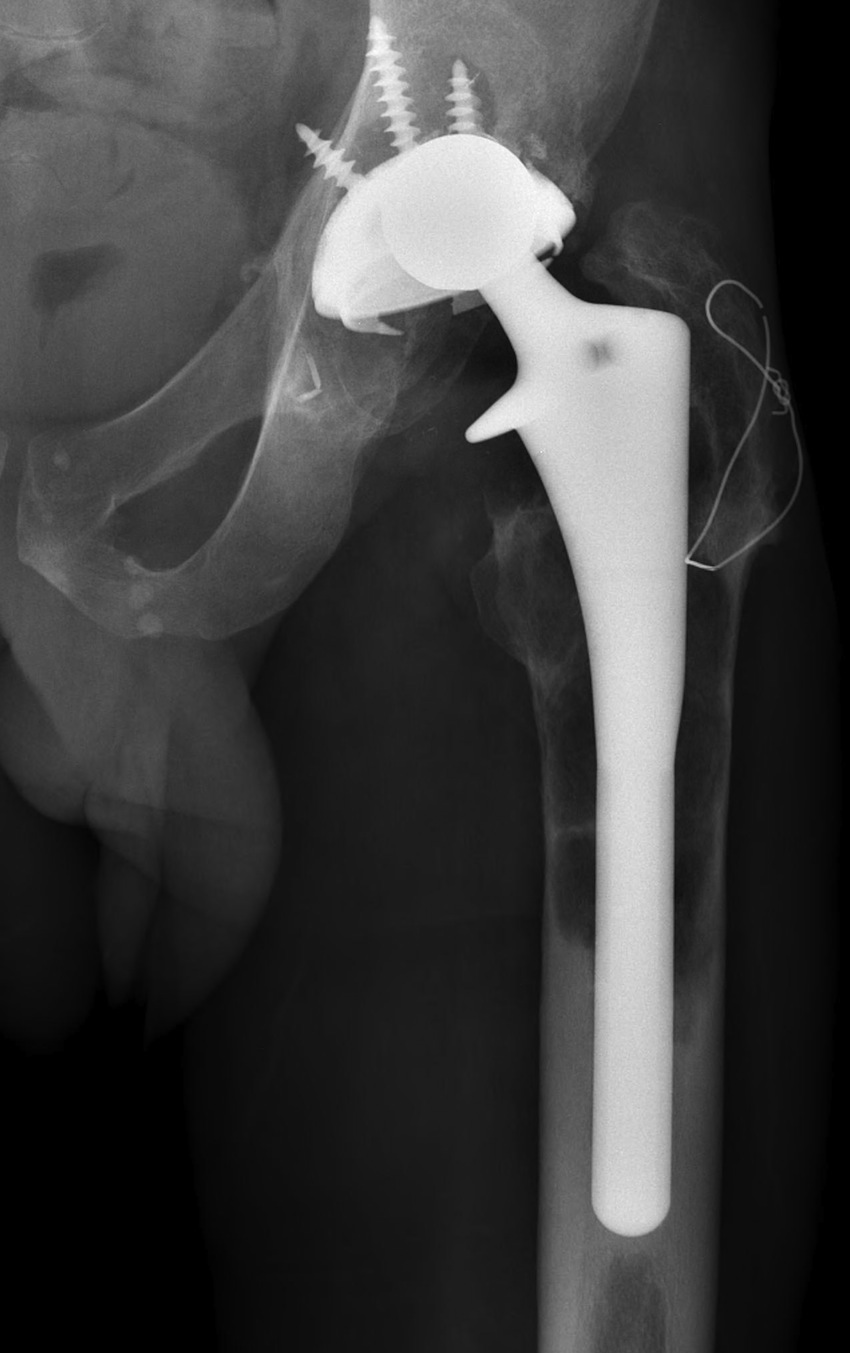

C. Proximal Femoral Replacement / Tumour prosthesis

D. Bulk Structural Proximal Femoral Allograft

Technique

- desired stem cemented into allograft

- press fit distally into host femur

- step cut graft host junction

- secure cerclage wire and onlay cortical strut

- proximal host bone wrapped around allograft with ABD preservation

- very important – abductor mechanism must be secured and protected